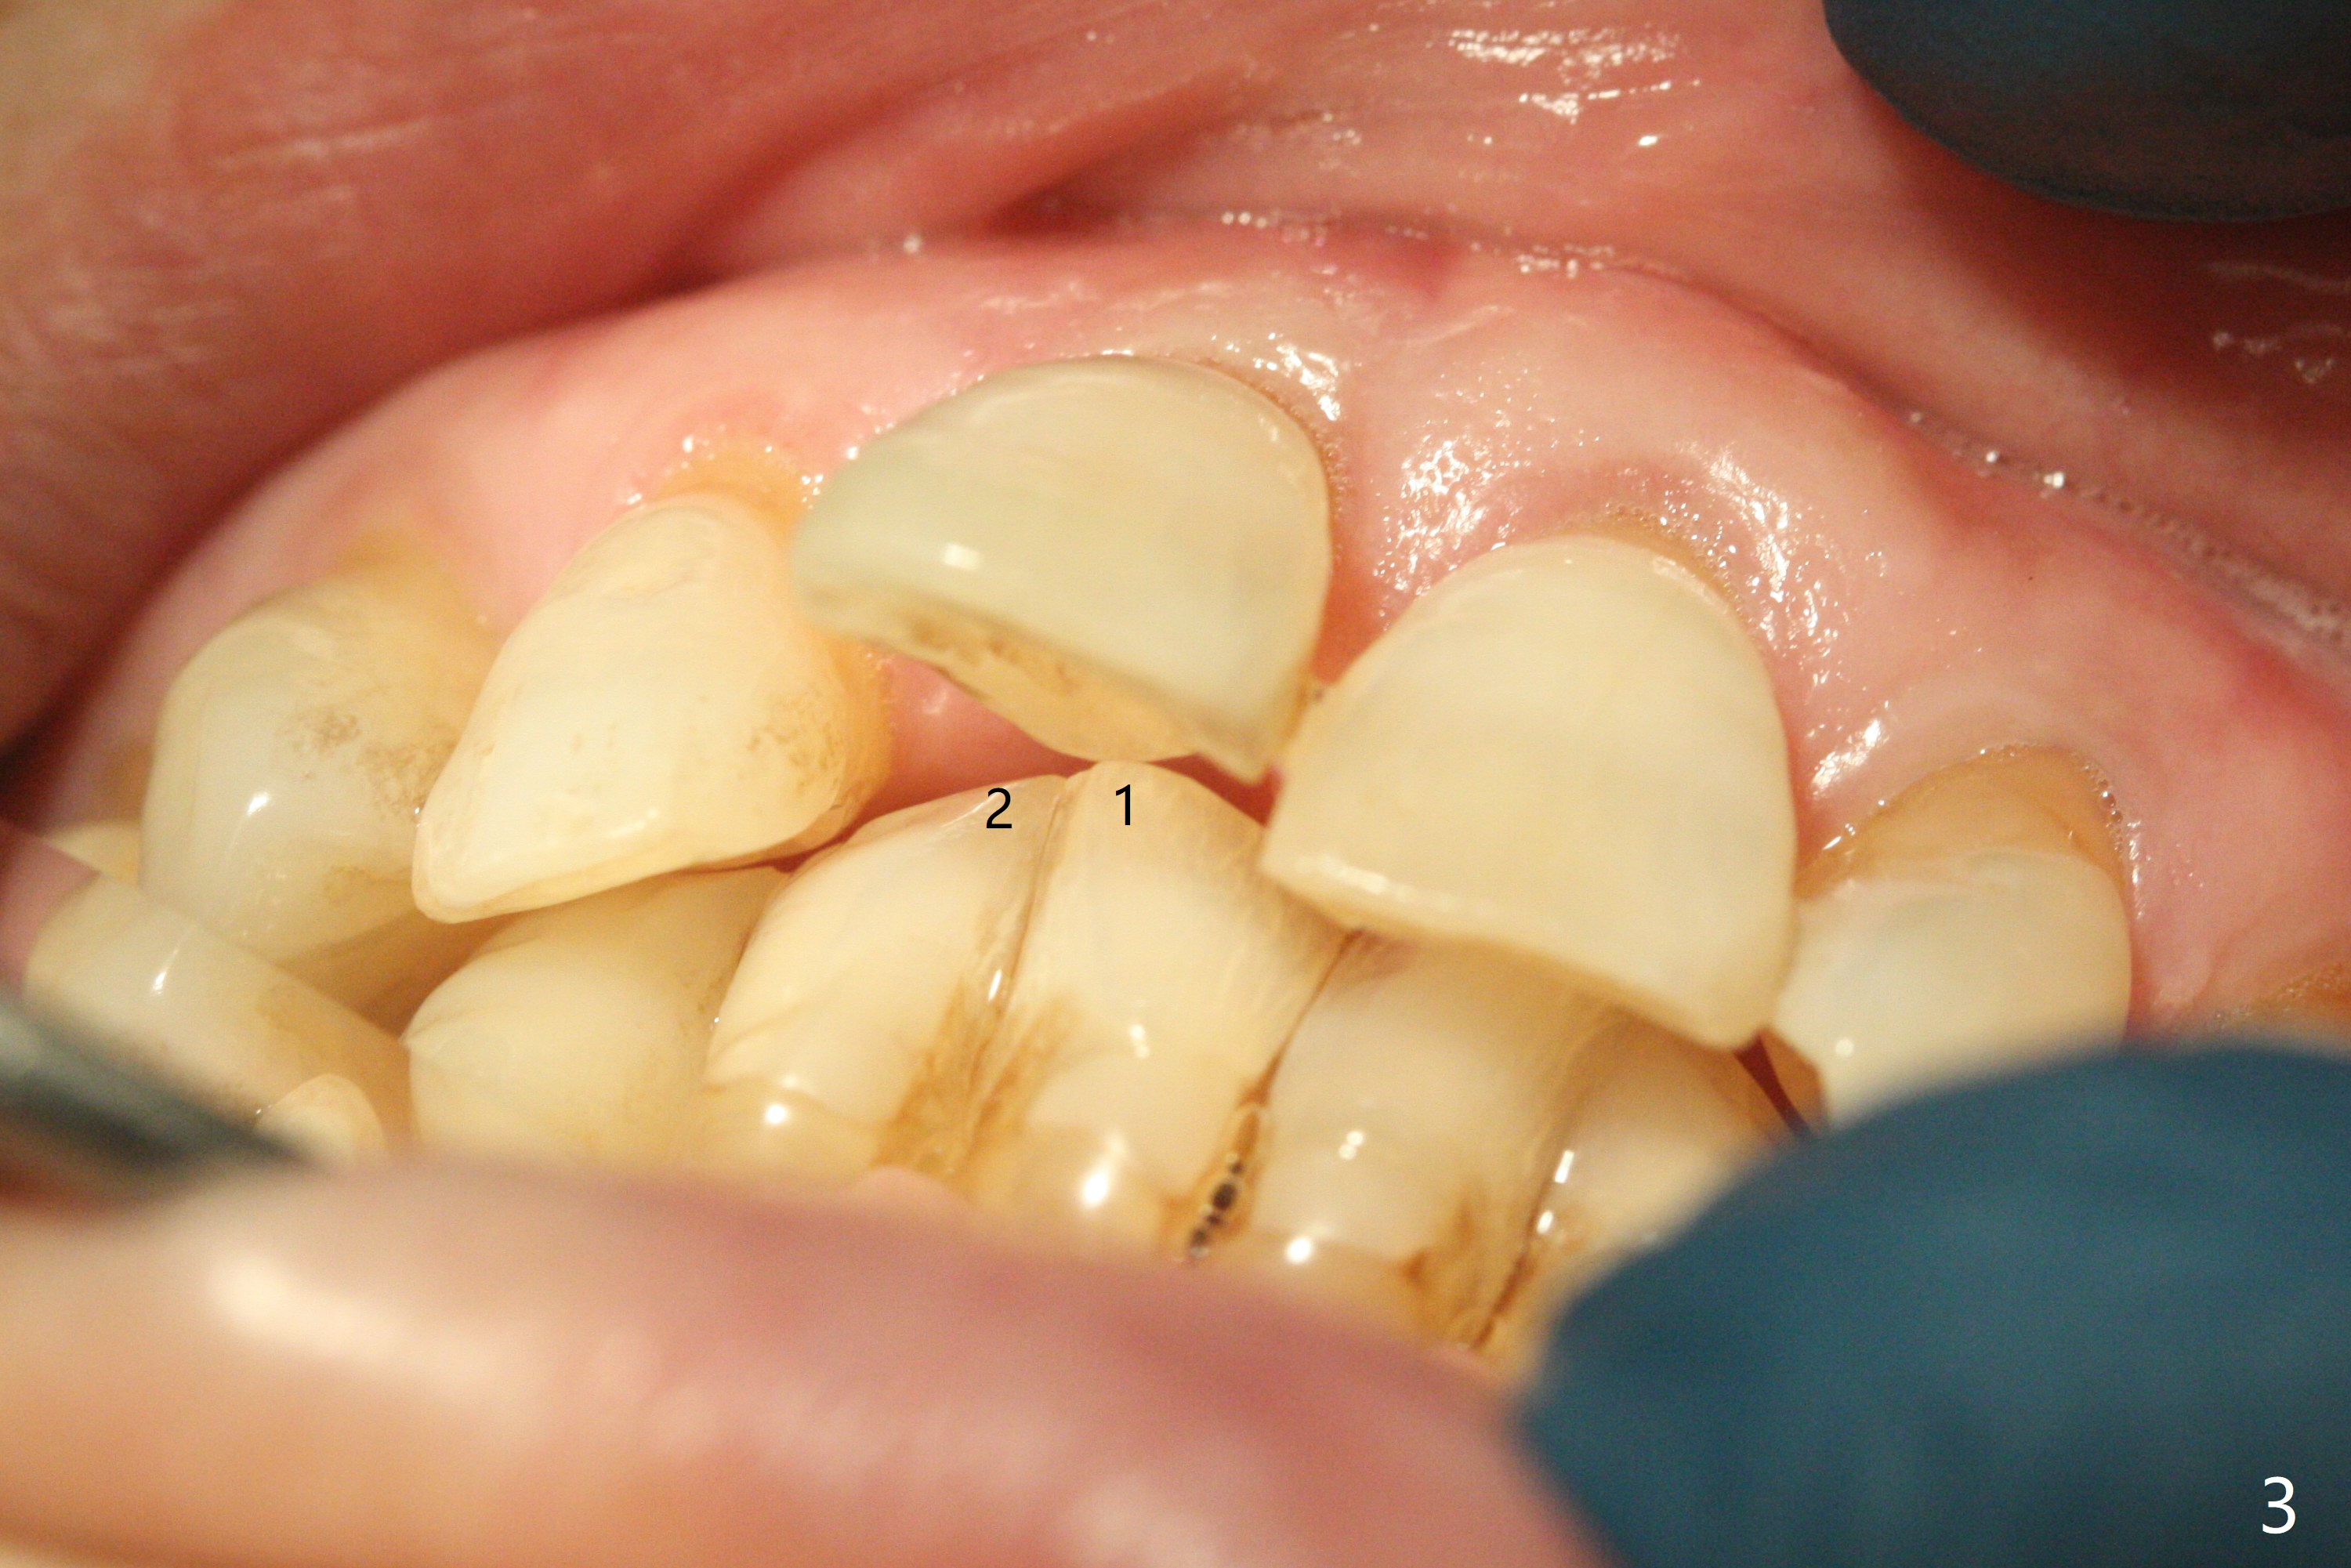

59岁女今天就诊,“上门牙快掉下来”,检查表明右上1延长(图一:长箭头),牙龈退缩(短箭头),红肿(*),颊侧骨板触诊不觉得塌陷(图二)。咬合时,患牙前移(图三),伸长的下切牙(图三,九:1,2)造成咬合创伤。因此拔牙前,将降低下门牙切缘(图四,五(黑色)),为临时牙冠创造足够修复空间。CT冠状切面显示颊侧(图六:B)骨板缺失,可以植入两段式植体(3.5x11.5 毫米),但是最细基台(4毫米直径,图七(粉红色和蓝色))显得太粗,不利于腭侧修复空间形成,而2.5x14(4)毫米一段式植体不仅创造更多颊侧植骨空间(图八(红箭头)),而且由于固有基台直径小(白箭头),容易形成腭侧修复空间。一旦前牙植体永久性修复完成,督促病人做三个第二磨牙植牙修复(图九:7),减少对前牙植牙创伤。临时牙冠不仅解决美观问题,而且固定骨粉,保持颊侧骨板隆起,维持牙龈缘和乳头。在大多数情况下,使用现成树脂牙冠(crown form)制作临时修复物,这个病例牙齿完整,截除的牙冠可以用来做临时牙冠。